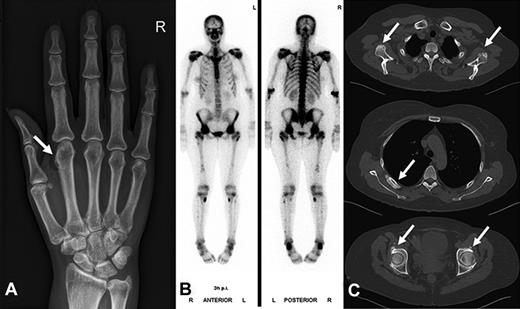

Radiographic findings and bone scintigraphy in patient 2. (A) Plain film showing marked periosteal bone apposition on radial and distal diaphysis of the first metacarpal bone of the right hand (arrow). (B) Technetium 99m-methyl-diphosphonate bone scintigraphy showing marked tracer uptake in the entire skeleton, most pronounced in the spine and pelvis. There are active spots in bones of both hands and feet. (C) CT scan of the entire skeleton revealed bone appositions in various sites of the skeleton (arrows): at the caudal margin of the glenoid (top), at the dorsal ribs (middle), and periacetabular on both sides (bottom). Findings are typical of hypertrophic osteoarthropathy.

We report 3 patients on long-term voriconazole treatment who developed clinically significant skeletal disease, which was completely reversible after termination of voriconazole (Table 1). All 3 patients were female allogeneic stem cell transplant recipients with cyclosporine-related moderate chronic renal failure. Disseminated bone pain started between 3 and 7.5 months of voriconazole treatment. Laboratory findings included an elevated alkaline phosphatase and bone-specific alkaline phosphatase, normal levels of calcium, phosphate, parathyroid hormone, 25-hydroxyvitamin D, and a slightly elevated urinary deoxypyridinoline/creatinine quotient. Conventional radiographs, CT scans, and bone scintigraphy revealed periosteal appositions and focal tracer uptake, respectively (Figures 1 and 2). CT scans of the chest and abdomen showed no signs of secondary malignancies, and bone marrow biopsies ruled out recurrence of the acute leukemia. Patients 1 and 2 were initially misdiagnosed as having an unusual musculoskeletal presentation of GVHD; hence, the immunosuppression was intensified. However, the pain was only temporarily attenuated by corticosteroids and methotrexate but disappeared almost completely in all 3 patients within 4 days of voriconazole cessation. The diagnosis of voriconazole-induced skeletal disease was made only retrospectively in patient 1, 20 months after occurrence of the first symptoms in patient 2, and without delay in patient 3. Serum fluoride measurements at diagnosis were available for patients 2 and 3 with > 10-fold elevated levels and a marked decrease within 3 weeks of voriconazole cessation (81% and 57% of precessation values, respectively). Long-term follow up of 5.5 years after the initial diagnosis revealed complete resolution of the skeletal changes in patient 1 (Figure 1).